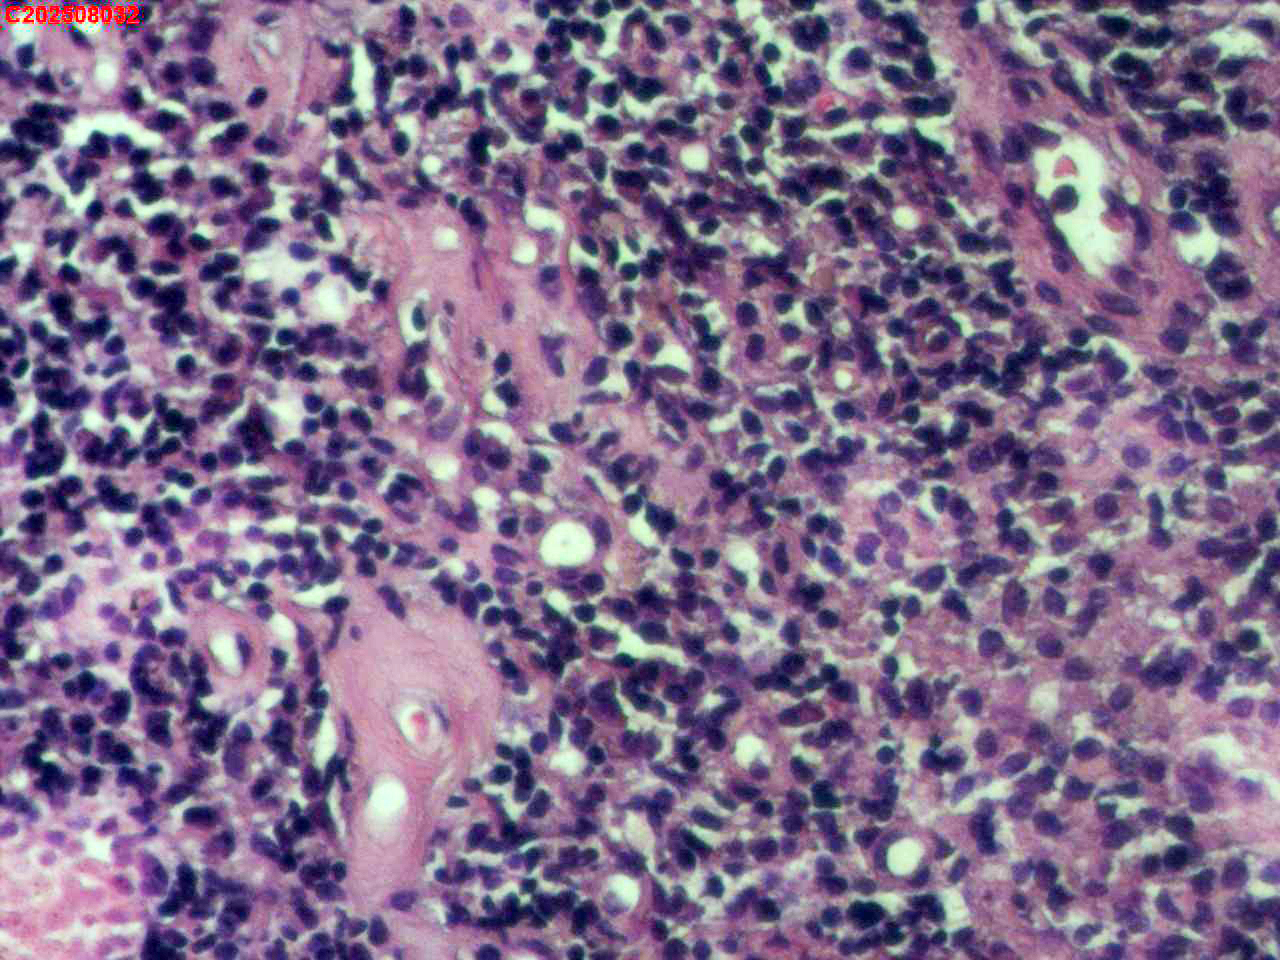

腹股沟淋巴结穿刺 临床:皮肤结核

性别

女

年龄

38岁

临床诊断

皮肤结核

一般病史

双下肢近踝关节处可见硬结,质硬,高出皮肤,局部皮温增高,触痛明显,双侧颈部、锁骨上、腋下、腹股沟区可触及多个大小不等肿大淋巴结,质软,无触痛,与周围组织无粘连,最大者为右侧腹股沟区可触及2×1cm淋巴结。

标本名称

腹股沟淋巴结穿刺

大体所见

腹股沟淋巴结穿刺,长度为:0.8cm×0.1cm